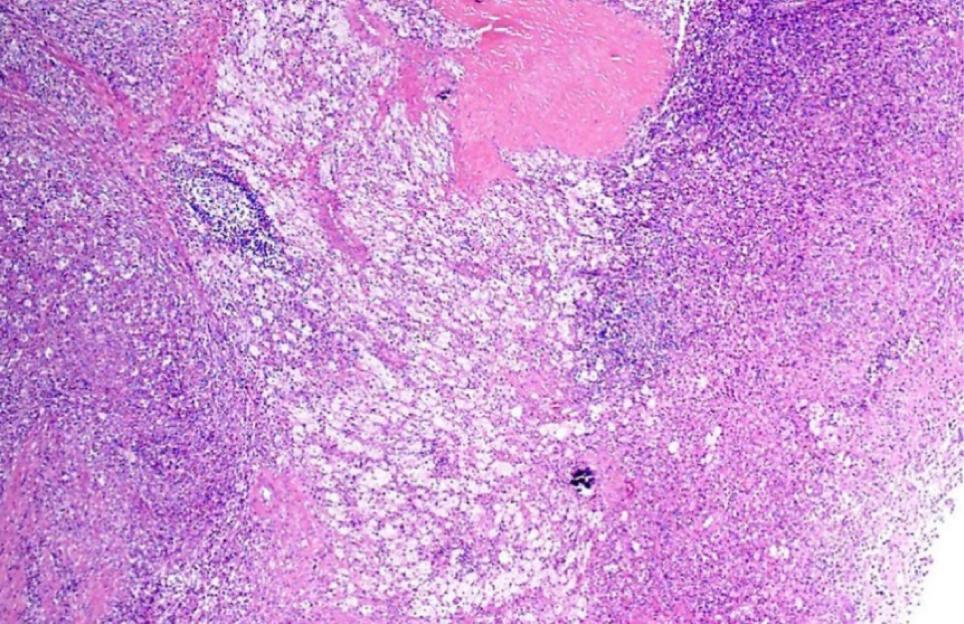

Figure 2: Photomicrograph image showing the renal parenchyma infiltrated with dense inflammation and foam cells on low magnification, suggestive of XGP on H&E staining.

XGP is a relatively rare subtype of chronic pyelonephritis with varying occurrences, which range between 0.6% and 1% as reported in literature (1). XGP is usually diffused (involving most of the kidney), and focal variant is less common. All age groups may be affected, but it is more commonly spotted in middle-age and elderly patients. XGP has been more commonly reported in females (11). Our study too observed that XGP is more common in females as compared to males. All the patients had unilateral presentation, as bilateral presentation is rarely encountered (2). Obstruction of the urinary tract and recurrent urinary tract infection (UTI) are common in XGP (1). A study conducted in India reported that nephrolithiasis was observed in 90% of XGP patients (12). Similarly, in our study nephrolithiasis was observed in nine (60%) patients. Diabetes mellitus, urinary stasis because of obstructive pathologies, renal neoplastic lesions, and immunocompromised attributes predispose patients to XGP (13,14). In the present study, diabetes was diagnosed in six (40%) patients and none of our patients was on immunosuppressive medications or had underlying malignancy. Varying clinical presentations have been observed in different studies. All the patients had abdominal pain on presentation, which is similar to most of the published series (7,12,14). In a recent study, pyonephrosis and perinephric abscess were observed in 25.0% and 7.5% patients, respectively (12), whereas in our study, three (20%) patients had pyonephrosis and three had perinephric collection. In a study conducted in Turkey, leukocytosis was observed in one (7.7%) patient, pyuria was diagnosed in six (46.1) patients, and 46.1% patients were anemic (15). Korkes et al. (5) analyzed 41 patients of XGP, in which anemia, pyuria, and leukocytosis were reported in 63%, 57.6%, and 41% of cases, respectively. In our study 11 (73.3%) patients were anemic, leucocystosis was diagnosed in 9 (60%), and all the patients had pyuria. In a study conducted by Kundu et al. (12), XGP was diffused in 31 (77.5%) patients and focal in 9 (22.5%) cases whereas in our study, diffused XGP was observed in 11 (73.3%) patients, which was similar to their study. Moreover, they observed biopsy diagnosis of XGP in 23 (57.5%) patients, 10 (25.0%) patients had pyonephrosis with XGP, 3 (7.5%) had XGP with diabetic nodular glomerulosclerosis, and 1 patient had renal cell carcinoma with concomitant XGP(12). In our study, pyonephrosis with XGP was noted in three patients whereas another three had perinephric collection. Diabetic glomerulosclerosis with XGP was observed in one of the six diabetic patients in our study, and none of our patients had neoplastic lesions. XGP has been divided into three stages: stage I is nephric XGP, which is confined to the renal parenchyma; stage II is perinephric XGP, having involvement of the anterior perirenal fascia, or Gerota’s fascia; and stage III is paranephric XGP, having involvement of the pararenal space and retroperitoneal structures (16). In the present study, 12 patients had stage I disease and 3 patients had stage II disease. Histopathologic examination of XGP determined an admixture of lipid-laden foamy macrophages with infiltration of varying mixtures of inflammatory cells along with fibrotic changes and cholesterol deposition. We too observed most of these changes in our specimens.